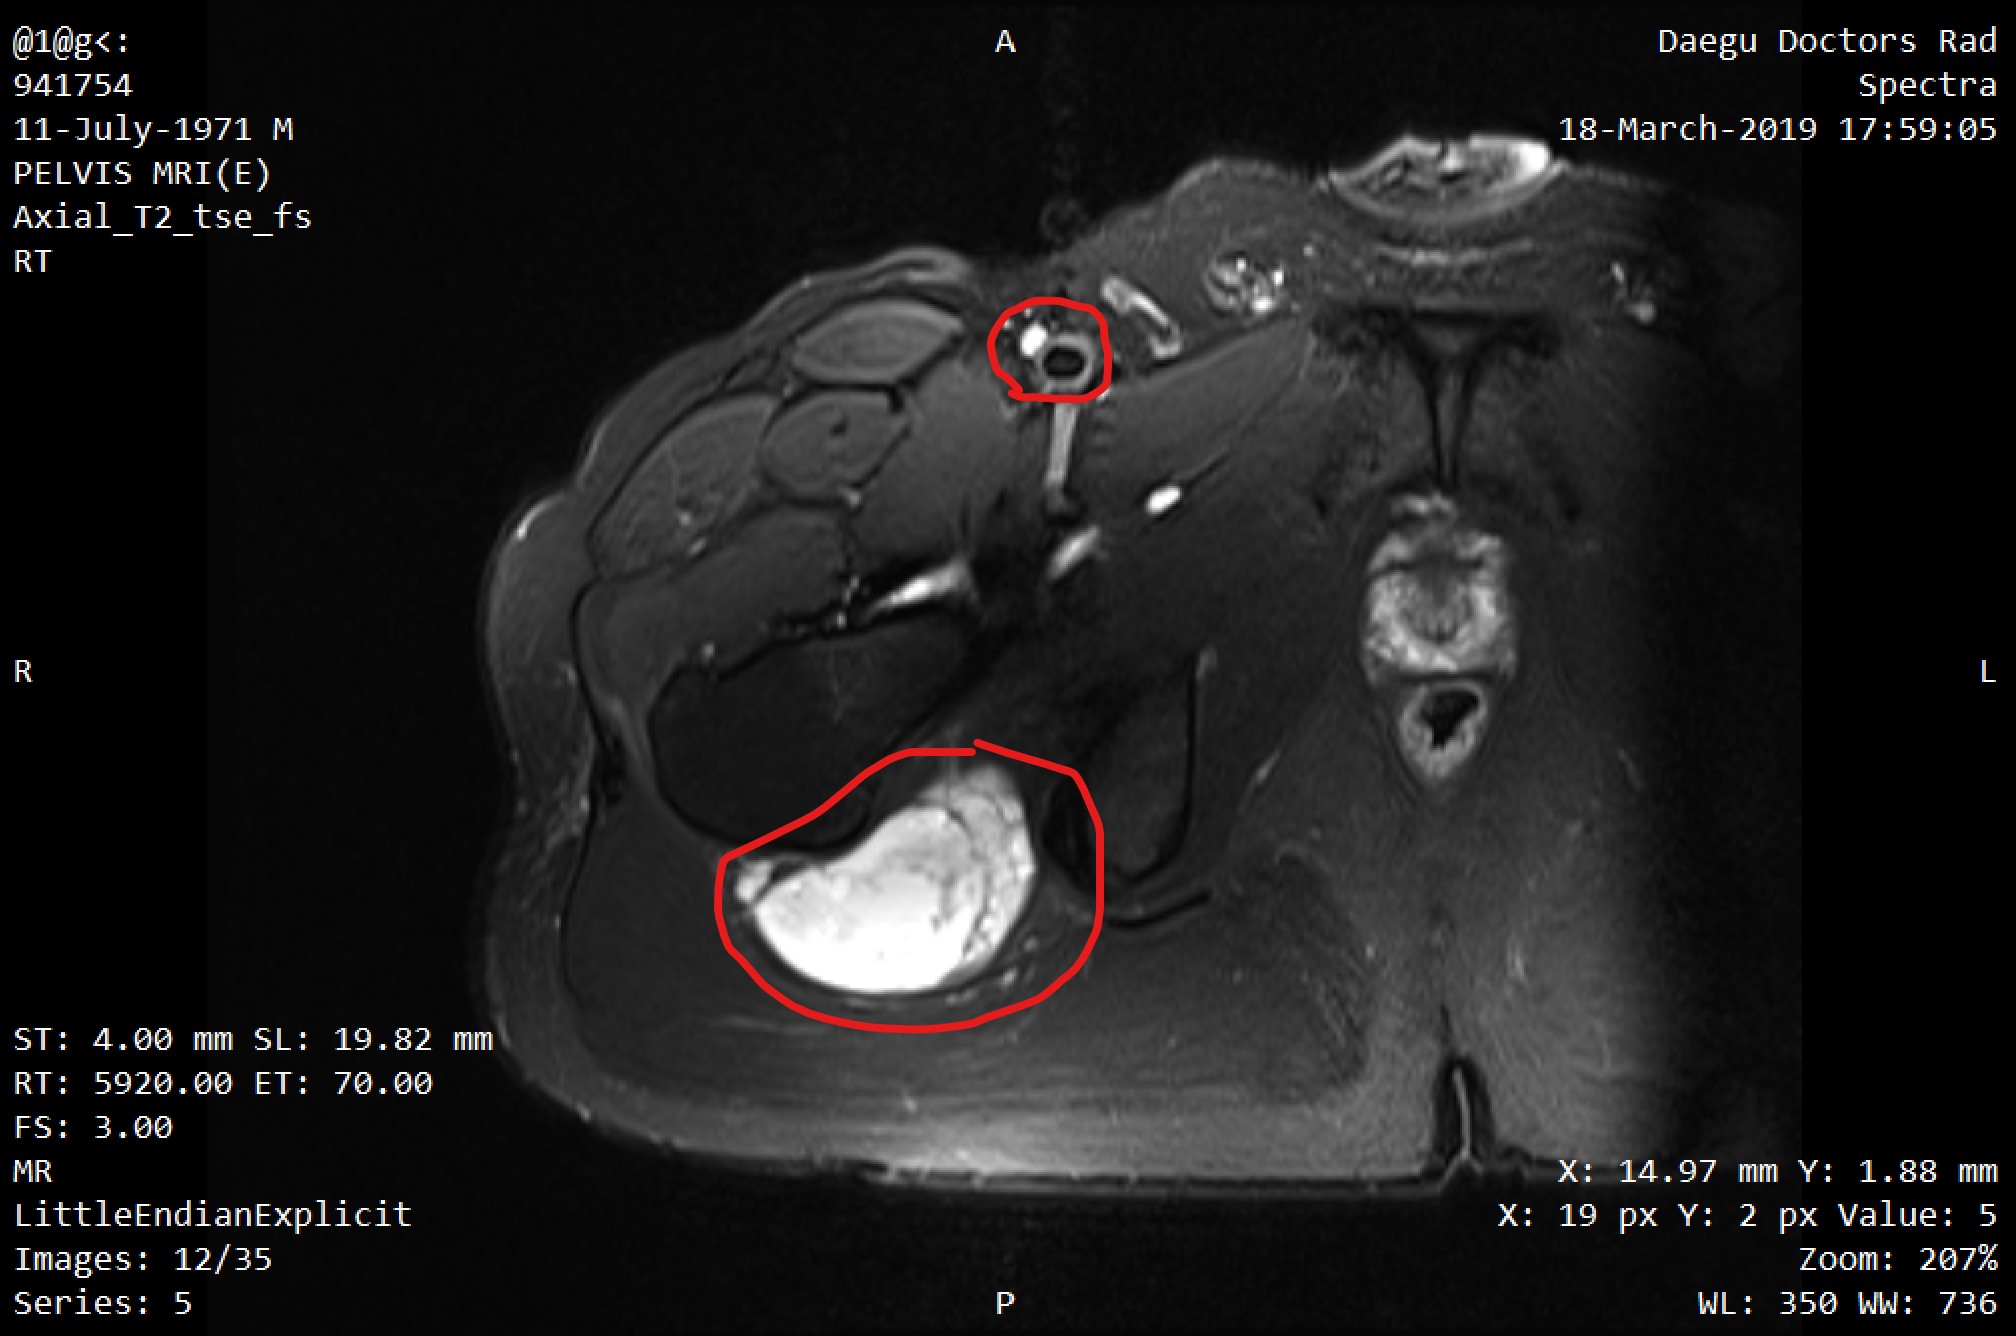

1. 우측 허벅지 MRI T2영상입니다. 허벅지 부분의 하얗게 표시된 부분이 육종암이고 상부에 조그만 검은 원형이 아마 혈관이고 그옆에 하얗게 보이는 부분이 림프전이된 내용으로 추정합니다

그날 그 MRI 영상을 갖고 대구 쪽 대학병원 정형외과 교수님, 혈액종양내과 교수님, 영상의학과 전문의, 처남이 모여 영상 보고 회의를 했단다. 그런 결과 육종암이 맞고 서혜부 쪽 림프 전이도 있는 거 같다는 의견이었다. 처음 MRI를 볼 땐 뭐가 뭔지 몰랐는데 계속 보다 보니 조금씩 보인다. 확실히 T2 영상이 더 잘 보이는 거 같다. (MRI는 T1과 T2 영상이 있다고 한다. 보통 T2 영상은 수분을 하얗게 보여줘서 종양을 찾기 쉽고, T1 영상은 조영제를 넣었을 때 결절 부위가 도드라져 보인다고 한다. 이번에 보니 확실히 T2 영상에서 병변이 더 잘 보이는 것 같다._해당 내용은 다시 정리해 올리도록 하겠습니다.)